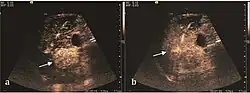

The suggestive appearance of early HCC on 2D ultrasound examination is that of hypoechoic nodule, with distinct pattern, developed on cirrhotic liver. Hypoechoic appearance is characteristic of moderate/poorly differentiated HCC, with low or absent fatty changes. Rarely, HCC may appear isoechoic, consist of a tumor type with a higher degree of differentiation and therefore with slower development. Another common aspect is "bright loop" or "nodule-in-nodule" appearance, hypoechoic nodules in a hyperechoic tumor.

Spectral Doppler characteristics of early HCC overlap those of the dysplastic nodule, as they are represented by the presence of portal venous signal type or arterial type with normal RI (well differentiated HCC) or increased RI (moderately or poorly differentiated HCC). The CFM exploration identifies a chaotic vessels pattern.

On CEUS examination, early HCC has an iso- or hypervascular appearance during the arterial phase followed by wash out during portal venous and late phase. There are studies showing that the wash out process is directly correlated with the size and features of neoplastic circulatory bed. Thus, highly differentiated HCC illustrates the phenomenon of late or even very late "wash out" while poorly differentiated HCC has an accelerated wash out at the end of arterial phase. It is therefore mandatory to analyze all these three phases of CEUS examination for a proper characterization of liver nodules. Tumor wash out at the end of the arterial phase allows the HCC diagnosis with a predictability of 89.5%. Some authors consider that early pronounced contrast enhancement of a nodule within 1–2 cm developed on a cirrhotic liver is sufficient for HCC diagnosis. These results prove that for a correct characterization of the lesions it is necessary to extend the examination time to 5 minutes or even longer.